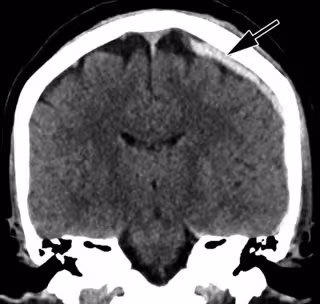

"La radiología ha hecho contribuciones sustanciales a la detección de traumas no accidentales en niños, y la identificación de la violencia pediátrica es un componente esencial de la capacitación de un radiólogo, pero se sabe poco sobre el papel de las imágenes en la detección de la violencia de pareja", afirma el investigador principal del estudio, Bharti Khurana, radiólogo del Hospital Brigham y de Mujeres y profesor asistente de radiología en la Escuela de Medicina de la Universidad de Harvard, en Boston, Estados Unidos. "Las imágenes médicas pueden ofrecer pistas tempranas de IPV según la ubicación y el patrón de las lesiones nuevas y antiguas", añade.

Los científicos descubrieron que casi todas las víctimas de violencia de pareja eran mujeres (96 por ciento). Las víctimas tenían una edad media de 34,2 años. El 37 por ciento eran afroamericanas y el 28 por ciento eran hispanas. Las víctimas de violencia por parte de su pareja, en promedio, se sometieron a aproximadamente cuatro veces más exámenes de imágenes en los cinco años anteriores en comparación con el grupo de control. Las fracturas agudas y los hallazgos obstétricos/ginecológicos, como pérdida del embarazo y restricción del crecimiento intrauterino, se asociaron con de dos a cuatro veces más probabilidades de violencia doméstica.

El objetivo final de la investigación, según Khurana, es desarrollar un sistema integrado que use patrones derivados del análisis experto de imágenes clínicas y datos clínicos, detecte y clasifique las lesiones, y avise automáticamente a los médicos clínicos si las lesiones de un paciente tienen un nivel bajo o probabilidad de alto riesgo de ser el resultado de la violencia machista.